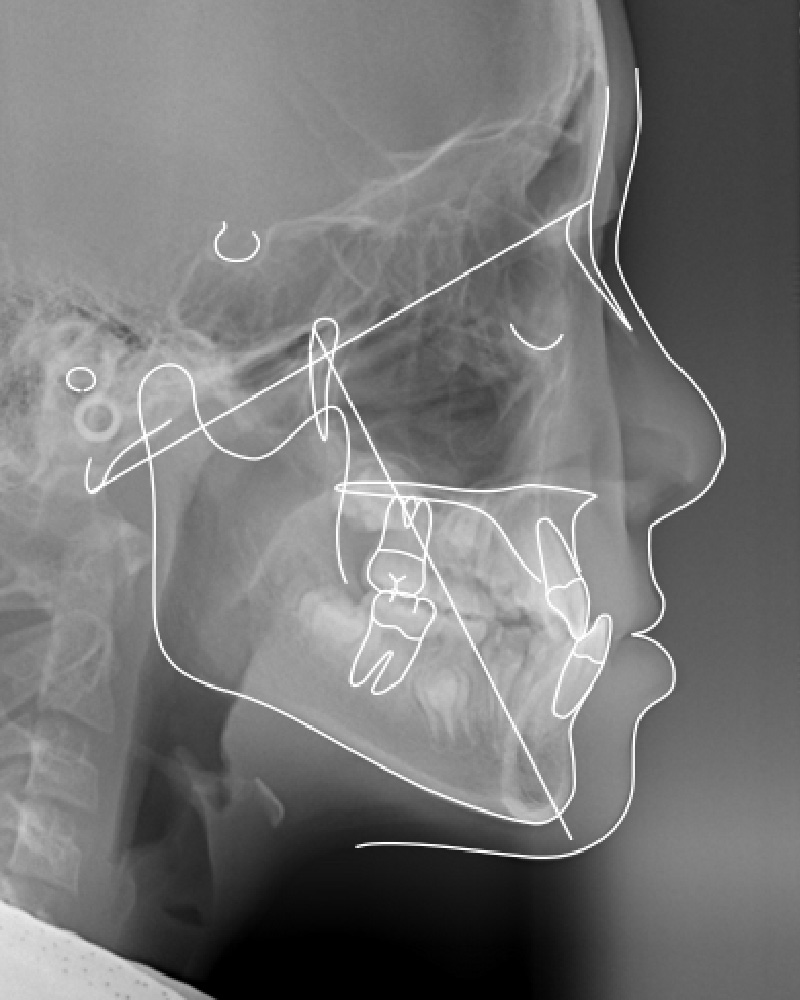

頭部X線規格写真

上顎の前方への成長を誘導した結果、治療前は歯を失ったお年寄りのような横顔が、治療後はふっくらとした顔立ちになり、大きく変化しました。